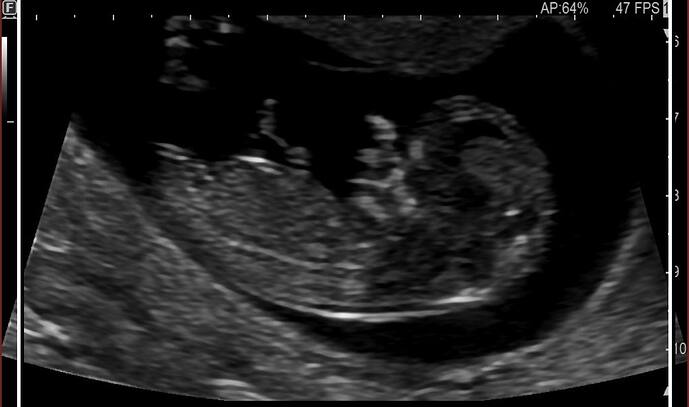

Kız iki çizgi var

cinsel organı düz 80 derece aşağına bence kız